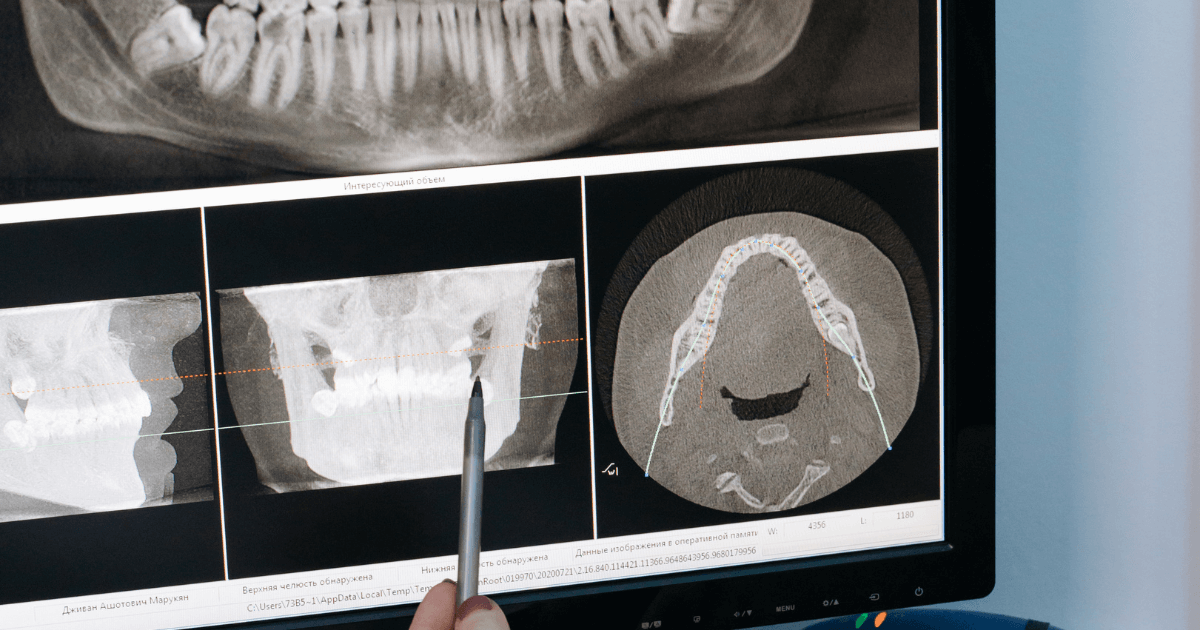

一方で、副鼻腔の不調や神経痛、筋のこりなど歯以外が関わるケースもあります。見分けるには叩いた時の反応、噛み合わせ紙の跡、レントゲンやCT、拡大視野での確認が役立ちます。